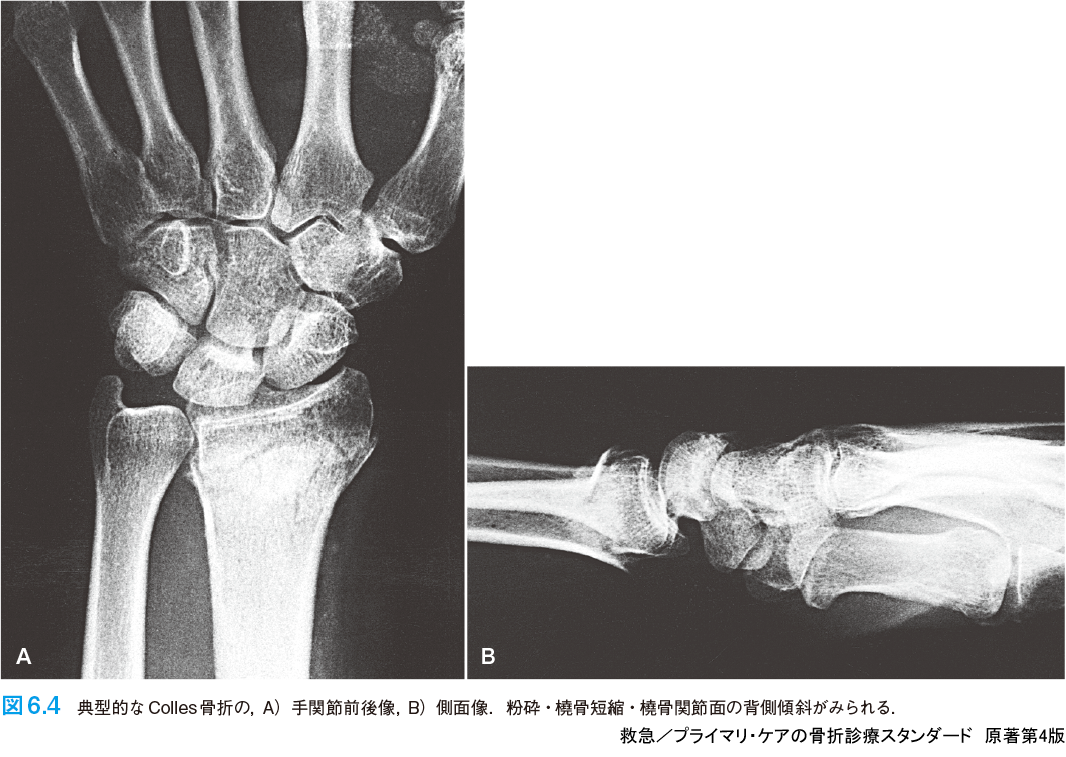

救急/プライマリ・ケアの骨折診療スタンダード 原著第4版 | 仲田 和正, M. Patrice Eiff, Robert L. Hatch, 舩越 拓, 吉田 英人 |本 | 通販 | Amazon,

救急/プライマリ・ケアの骨折診療スタンダード 原著第4版 | 仲田 和正, M. Patrice Eiff, Robert L. Hatch, 舩越 拓, 吉田 英人 |本 | 通販 | Amazon, 救急/プライマリ・ケアの骨折診療スタンダード 原著第4版 | 仲田 和正, M. Patrice Eiff, Robert L. Hatch, 舩越 拓, 吉田 英人 |本 | 通販 | Amazon,

救急/プライマリ・ケアの骨折診療スタンダード 原著第4版 | 仲田 和正, M. Patrice Eiff, Robert L. Hatch, 舩越 拓, 吉田 英人 |本 | 通販 | Amazon, 救急/プライマリ・ケアの骨折診療スタンダード 原著第4版 - 羊土社,

救急/プライマリ・ケアの骨折診療スタンダード 原著第4版 - 羊土社, 救急/プライマリ・ケアの骨折診療スタンダード 原著第4版 - 羊土社,

救急/プライマリ・ケアの骨折診療スタンダード 原著第4版 - 羊土社, ERでの創処置 縫合・治療のスタンダード 原著第4版 | Alexander T.Trott, 岡 正二郎 |本 | 通販 | Amazon